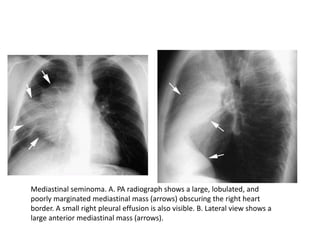

Mediastinal seminoma. A. PA radiograph shows a large, lobulated, and

poorly marginated mediastinal mass (arrows) obscuring the right heart

border. A small right pleural effusion is also visible. B. Lateral view shows a

large anterior mediastinal mass (arrows).

Mediastinal seminoma. A.PA radiograph shows a large, lobulated, and poorly marginated mediastinal mass (arrows) obscuring the right heart border. A small right pleural effusion is also visible. B. Lateral view shows a large anterior mediastinal mass (arrows).